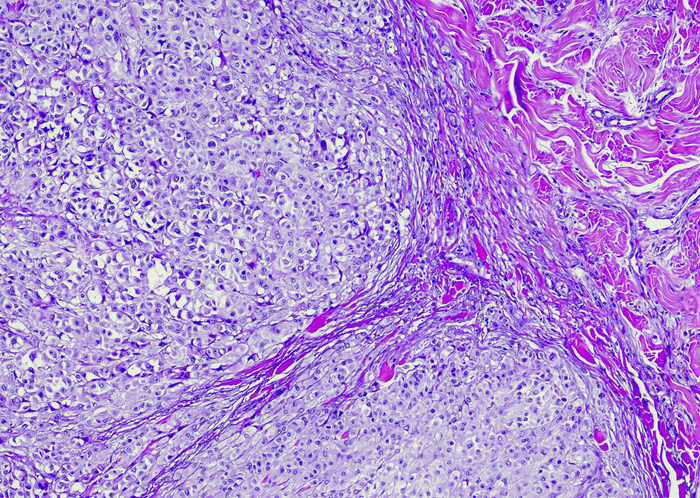

The study, which was published in the New England Journal of Medicine, has included 14 patients to date, all of whom had locally advanced rectal cancer with a mismatch repair deficiency (MMRd). “They lack a gene that enables them to repair their DNA and because of that, they have many, many mutations, and the immune system recognizes the cancer is foreign,” oncologist Andrea Cercek, a coauthor of the study from Memorial Sloan Kettering Cancer Center, tells CNN. “When we give immunotherapy, like dostarlimab, it really just revs up the immune system so that it sees the cancer and gets rid of it.”

The population of interest were treated with the novel, experimental immunotherapy dostarlimab (GlaxoSmithKline) over the duration of six months. The immunotherapy works not by attacking the cancer directly, but rather by augmenting the immune system to combat the disease. Subsequent to treatment, the cancer was undiscernible to every detection modality, from physical exam to MRI scan.